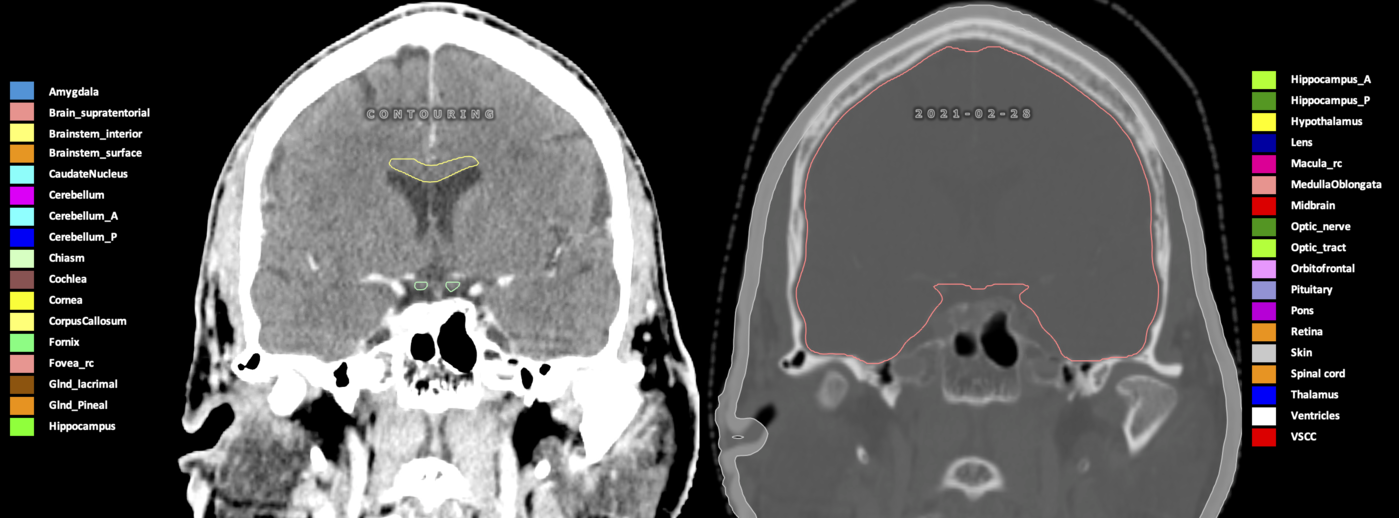

Eekers et al. have published an international neurological atlas for contouring of organs at risk in consensus with the European Particle Therapy Network (EPTN) in 2018 and an update in 2021. The purpose of this consensus atlas is to decrease inter- and intra-observer variability in delineating OARs relevant for neuro-oncology.

Included are all OARs known to be relevant for radiation-induced toxicity in neuro-oncology: brain, brainstem (midbrain, pons, medulla oblongata), chiasm, cerebellum (anterior & posterior), cochlea, cornea, hippocampus (anterior & posterior), hypothalamus, lens, lacrimal gland, optic nerve, pituitary, skin, and vestibular & semicircular canals. To further facilitate research on cognition, vision and radiological changes after irradiation of the brain, potential clinically-relevant OARs are included: amygdala, caudate nucleus, cerebellum (anterior & posterior), corpus callosum, fornix, macula, optic tract, orbitofrontal cortex, periventricular space (PVS), pineal gland, and thalamus.

Three-dimensional delineation of the 25 consensus OARs for neuro-oncology are shown on CT (WW/WL 120/40, 3000/600), 3T MR images, (T1Gd, T2FLAIR 1mm) and 7T MR (MP2RAGE 0.7 mm). All are presented in transversal, sagittal and coronal view.